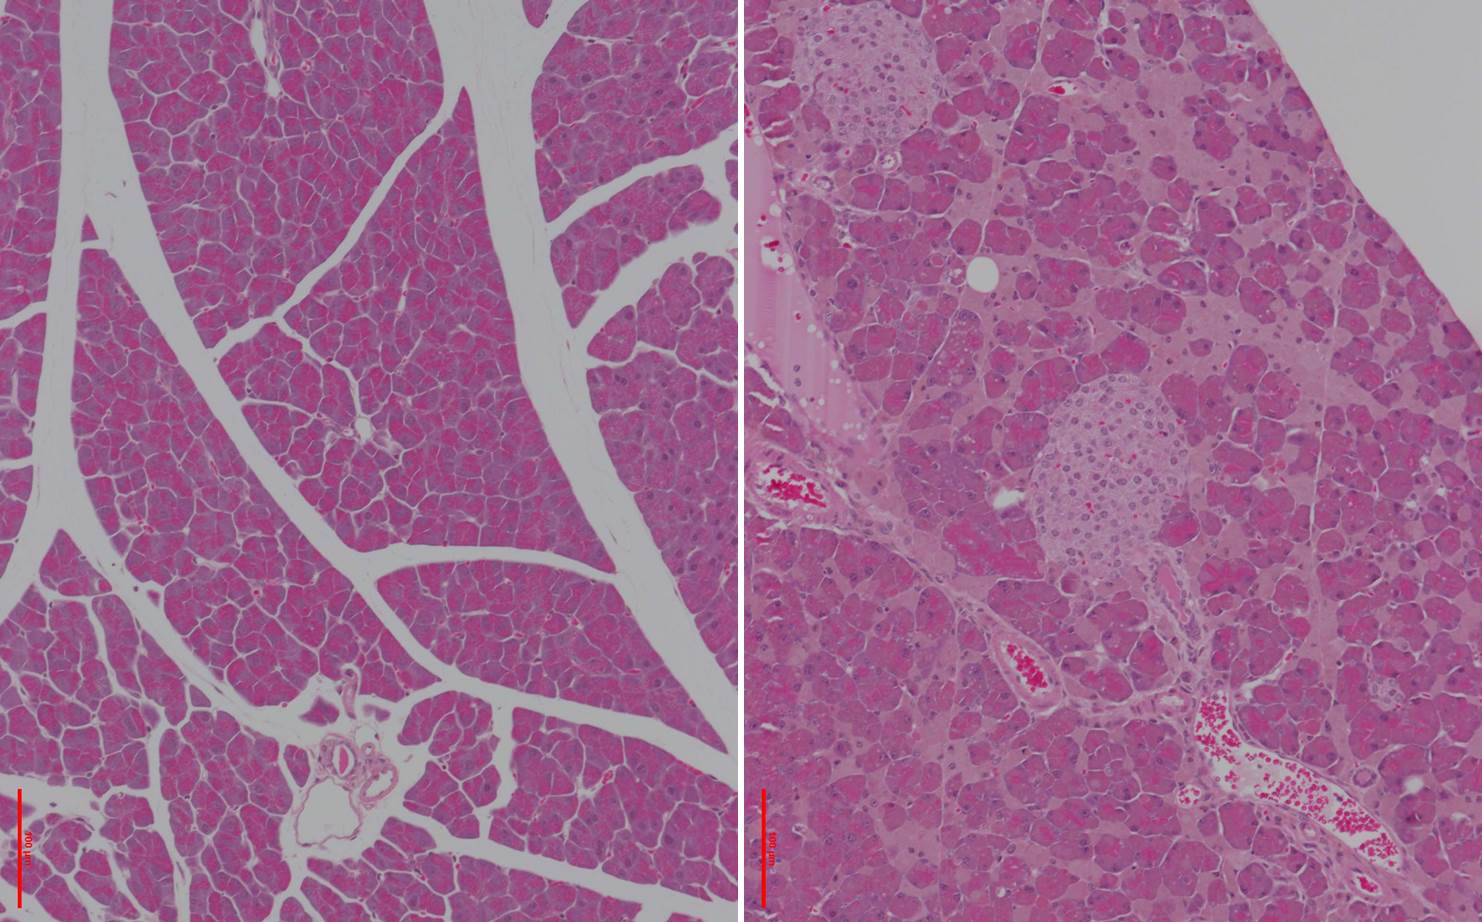

Bei den Mäusen ist ein einzelner Baustein, eine sogenannte Aminosäure, des Proteins Ferroportin ausgetauscht. „Diese kleine Veränderung stört die Interaktion zwischen Hepcidin und Ferroportin empfindlich und hat dramatische Auswirkungen auf den gesamten Eisenstoffwechsel“, erklärt Dr. Sandro Altamura (Universitätsklinikum Heidelberg), der das Tiermodell gemeinsam mit Dr. Bruno Galy (EMBL) entwickelt hat. Das Tiermodell soll nun dabei helfen, die Mechanismen der Hepcidin-Resistenz insgesamt besser zu verstehen. Im Tierversuch litt die Bauspeicheldrüse am meisten unter dem massiven Eisenüberschuss. Beim Menschen wird das Drüsengewebe zwar auch schwer geschädigt, allerdings schreitet die Zerstörung langsamer voran. „Durch den schnelleren Krankheitsverlauf im Mausmodell haben wir nun erstmals die Möglichkeit, die schädliche Wirkung des Eisens auf das Drüsengewebe des Pankreas genauer zu untersuchen und Ansatzpunkte für vorbeugende Therapien zu entwickeln“, so der Biologe.